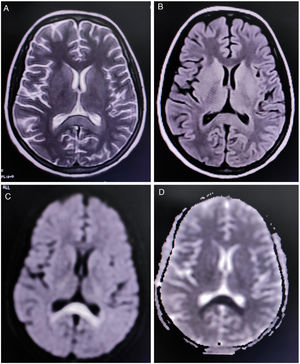

Complete blood cell count revealed mild anemia (hemoglobin 9.0g/dL), elevated erythrocyte sedimentation rate (80mm/h), relative lymphopenia, and thrombocytopenia (platelets count=60,000/μl (reference range 150,000–450,000). Liver function tests showed an approximately two-fold rise of the transaminases. Renal and thyroid function tests and blood glucose levels were within normal limits. Diagnostic tests were negative for endemic infections like malaria, dengue, Leptospira, Japanese encephalitis, and scrub typhus. However, Typhi Dot IgM (ELISA) was found to be positive. Magnetic resonance imaging (MRI) of the brain demonstrated a non-enhancing hypertense lesion on T2-weighted image and T2-FLAIR, with substantial diffusion restriction on diffusion-weighted imaging sequences, involving the splenium of the corpus callosum, suggestive of boomerang sign (Fig. 1). MR angiography of the brain was normal. Cerebrospinal fluid (CSF) studies revealed lymphocytic pleocytosis (10cells/μl, all lymphocytes), slightly low glucose levels (48mg/dL, normal range 50–80mg/dL), and normal protein levels (46mg/dL, normal range 15–50mg/dL) without any albuminocytologic dissociation. Oligoclonal bands, anti-aquaporin 4, and anti-myelin oligodendrocyte glycoprotein antibodies were not detected in the CSF and serum. However, serum GQ-1b-IgG antibodies were positive. CSF polymerase chain reaction for relevant neuroviruses and tuberculosis and tests for neurosarcoidosis and neuroborreliosis were negative. Tests for Mycoplasma, Campylobacter jejuni, influenza, HIV, and hepatitis viruses were also non-reactive. Sensory and motor nerve conduction studies revealed bilateral sensory-motor polyneuropathy, predominantly axonal; needle electromyography and repetitive nerve stimulation tests were unremarkable. Blood cultures resulted positive for Salmonella typhi.

Neuroimaging in this patient showed an uncommon radiological finding, i.e. cytotoxic lesion of the corpus callosum (CLOCCs), popularly known as the “boomerang sign”.8 CLOCCs, especially involving the splenium, are seen in association with cerebrovascular events, demyelinating disorders, metabolic disorders, seizures, medications, infections, malignancies, trauma, high-altitude cerebral edema, preeclampsia toxicity, posterior reversible encephalopathy syndrome, autoimmune encephalitis, post-partum cerebral angiopathy, and vaccination, among others.9,10